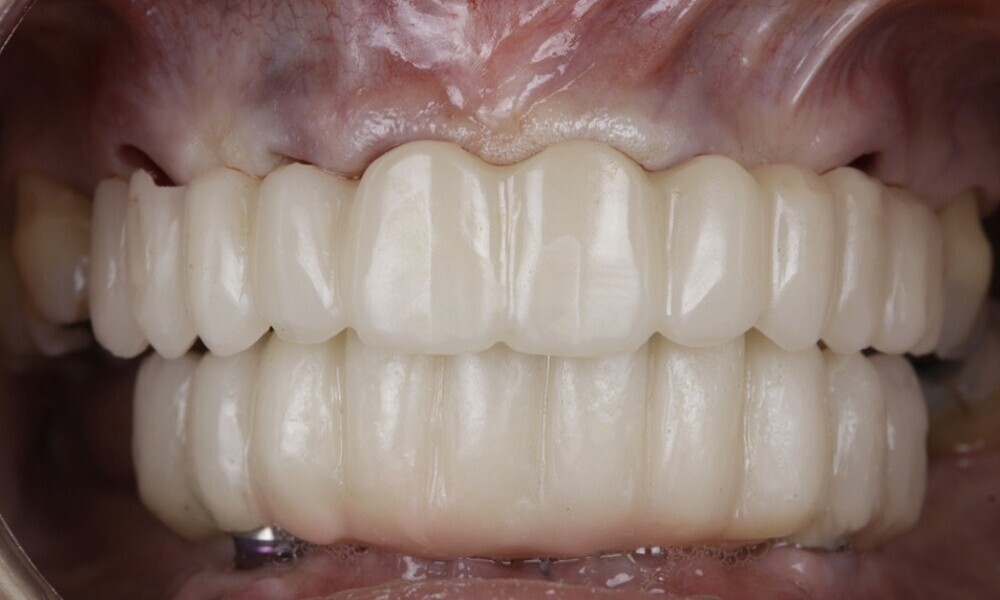

The soft tissue was in good condition, and the definitive restorations were placed (Figs. 76 & 77). After placing the definitive restorations, oral hygiene instructions were given to ensure proper care and prevent complications. Additionally, the occlusion was carefully checked and adjusted as needed (Figs. 78–83).

Figs. 78–82: The definitive restorations were placed, and occlusal adjustments were performed.

Fig. 83: The definitive restorations were placed, and occlusal adjustments were performed.